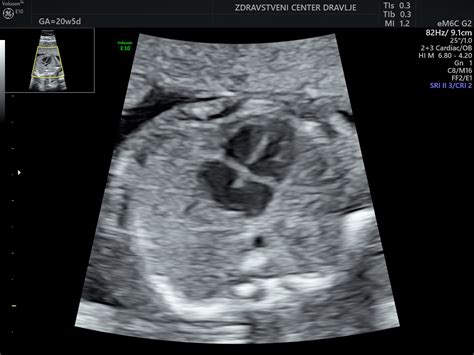

V šestem mesecu nosečnosti otrok meri med 30 in 35 centimetri in tehta približno 0,9 kg. V tem času se nadaljuje intenziven razvoj organov in sistemov, ki bodo otroku omogočili samostojno življenje.

Pluča se še naprej razvijajo; v njih nastaja snov, imenovana surfaktant, ki bo po rojstvu pomagala ohranjati odprte drobne zračne mešičke v pljučih (alveole). Otrok že vadi dihanje, kar lahko opazimo kot ritmične premike, čeprav še ne vdihuje plodovnice. Veke se ločijo in otrok lahko za kratek čas odpre oči, kar je pomemben korak v razvoju vida. Koža je še vedno prekrita z zaščitno belo mastno snovjo, imenovano verniks, ki jo ščiti pred plodovnico in pomaga pri uravnavanju telesne temperature po rojstvu. Otroku se lahko kolca, kar lahko občuti tudi mati kot nežne trzljaje. V črevesju se formira prvo blato - mekonij. Plod zazna zunanje zvoke in se nanje že odziva, kar pomeni, da se njegov sluh še naprej razvija. Če je bil vaš test nosečnosti pozitiven, vam čestitamo! Vaše misli so verjetno polne vprašanj, kot so, kako se bo spremenilo vaše telo in kako hitro se razvija otrok.